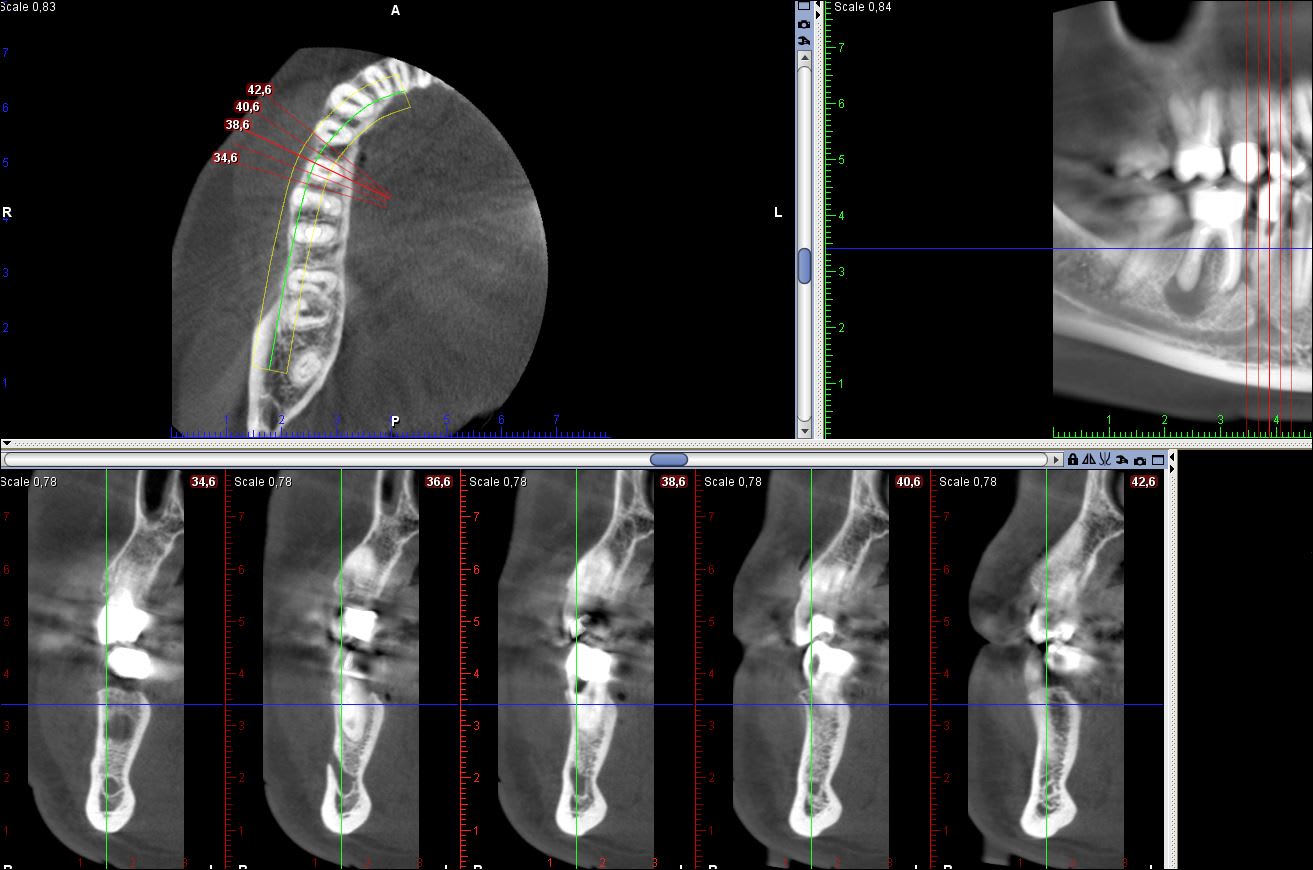

j'en profite pour poster mes rvg 2019 du précédents cas

L'endo était méga chiante, désolé avec une butée sur la 35, je vous laisse juge de la qualité du taitement

pour l'instant les symptomes ont disparus